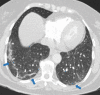

The coronavirus disease 2019 (COVID-19) pandemic is a global health care emergency. Although reverse-transcription polymerase chain reaction testing is the reference standard method to identify patients with COVID-19 infection, chest radiography and CT play a vital role in the detection and management of these patients. Prediction models for COVID-19 imaging are rapidly being developed to support medical decision making. However, inadequate availability of a diverse annotated data set has limited the performance and generalizability of existing models. To address this unmet need, the RSNA and Society of Thoracic Radiology collaborated to develop the RSNA International COVID-19 Open Radiology Database (RICORD). This database is the first multi-institutional, multinational, expert-annotated COVID-19 imaging data set. It is made freely available to the machine learning community as a research and educational resource for COVID-19 chest imaging. Pixel-level volumetric segmentation with clinical annotations was performed by thoracic radiology subspecialists for all COVID-19-positive thoracic CT scans. The labeling schema was coordinated with other international consensus panels and COVID-19 data annotation efforts, the European Society of Medical Imaging Informatics, the American College of Radiology, and the American Association of Physicists in Medicine. Study-level COVID-19 classification labels for chest radiographs were annotated by three radiologists, with majority vote adjudication by board-certified radiologists. RICORD consists of 240 thoracic CT scans and 1000 chest radiographs contributed from four international sites. It is anticipated that RICORD will ideally lead to prediction models that can demonstrate sustained performance across populations and health care systems.